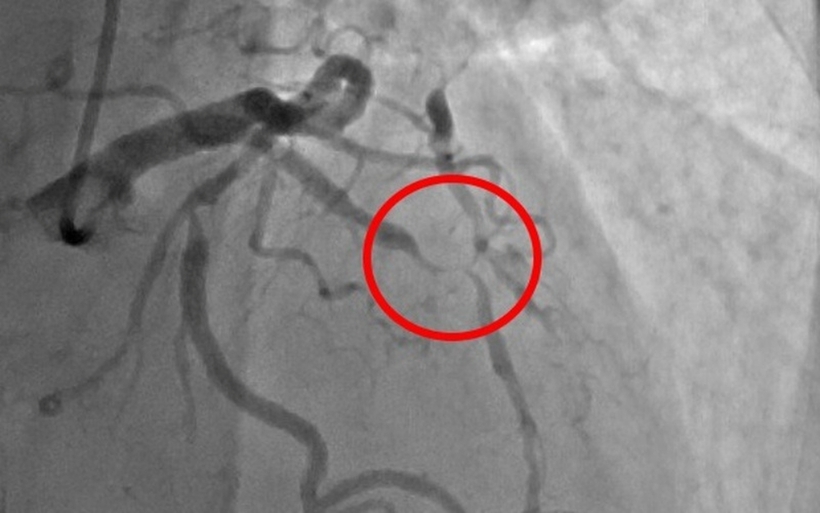

Hình ảnh mạch vành người bệnh trước can thiệp. Ảnh: VTV Times

Bệnh nhân được điều trị tích cực tình trạng suy tim, nhồi máu cơ tim, phối hợp kháng sinh, cân bằng nước điện giải. Ngay khi tình trạng khó thở cải thiện, chức năng thận ổn định, bệnh nhân được ekip can thiệp tiến hành chụp động mạch vành.

Kết quả chụp cho thấy bệnh nhân bị hẹp nặng cả ba nhánh động mạch vành (mạch máu nuôi tim). Sau đó, ekip can thiệp tư vấn rõ gia đình các phương pháp can thiệp mạch vành, nguy cơ, lợi ích của từng phương pháp.

Gia đình thống nhất lựa chọn phương pháp đặt stent động mạch vành. Với thủ thuật này, chỉ cần gây tê tại cổ tay nên trong và sau quá trình can thiệp, bệnh nhân hoàn toàn tỉnh táo.

Sau khoảng 45 phút, ekip can thiệp đã đặt thành công 2 stent vào nhánh động mạch vành - thủ phạm hẹp nặng và tắc gần hoàn toàn (nhánh liên thất trước) gây nên bệnh cảnh nhồi máu cơ tim cấp, suy tim cấp.